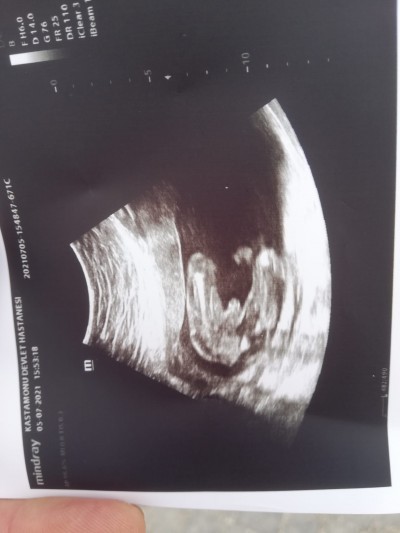

Merhaba 14+6 haftalık hamileyim  12. Haftada ikili tarama testinde ve cuma günü bebeğim kız çıkmıştı ama bugün doktor kesin erkek dedi fotoğrafı ekliyorum sizce yine değişir mi yoksa bu sefer kesin mi artık

Gebelik haftası 14+6

Yaa bilemedim sanki pipi icin biraz fazla buyuk gorunmuyor mu acaba kordonun yukari dogru cikmis hali olabilir mi bilemedim ama doktordan iyi bilemeyiz tabi kesin demis o tek bi fotografa bakmiyor sonucta evirip ceviriyor

12 de 14 te erkek denildi ve 16. Haftamda bende aynı fotoğraftan gördüm ve erkek canım. Değişmez artık çünkü net baya bence.

Bariz belli canim erkek oldugu benim bebegimin fotosunun aynisi degismedi seninde degisecegini sanmiyorum sağlıcakla al yavrunu canim

Bilemedim canım pipi için baya geniş duruyor kordon da olabilir 2 hafta sonra git kesinleşir .benim oğlumun alttan resmi de bu

Ay bende de aynı foto var :) 13. Haftada 2li testte erkek dedi.16 hafta oldu  başka  Dr a  gittim o da erkek dedi. Senin de erkek muhtemel hayırlı olsun sağlıkla gelsin İnş.